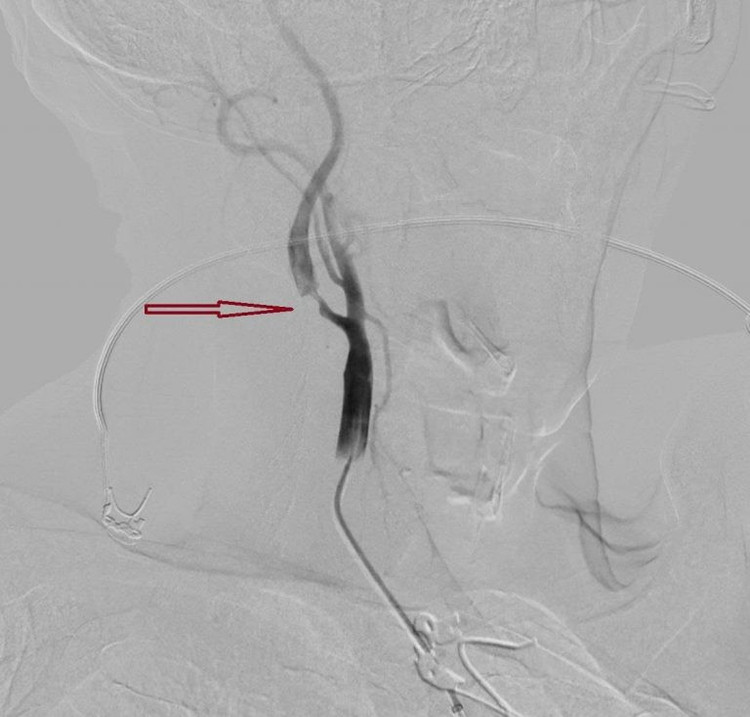

dot-quy-cao-3.jpg

Hình DSA cho thấy hẹp nặng đoạn gốc động mạch cảnh trong ngoài sọ trước can thiệp của bệnh nhân đột quỵ.

Trước tình thế nguy cấp, từng giây phút đều quý giá để bảo vệ các tế bào não và tính mạng cho bệnh nhân, bác sĩ khoa Sọ não cột sống 2 cũng được huy động kịp thời.

Song song đó, kết quả chụp CTA ghi nhận ông bị tắc động mạch não giữa M1 bên phải – một động mạch lớn, và hẹp nặng động mạch cảnh trong bên phải đoạn gốc.